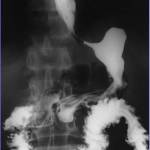

GIST Tumor on Fluoroscopy

Diagnosis: Gastrointestinal stromal tumor (GIST tumor)

Findings on Imaging:

On upper GI series, any...